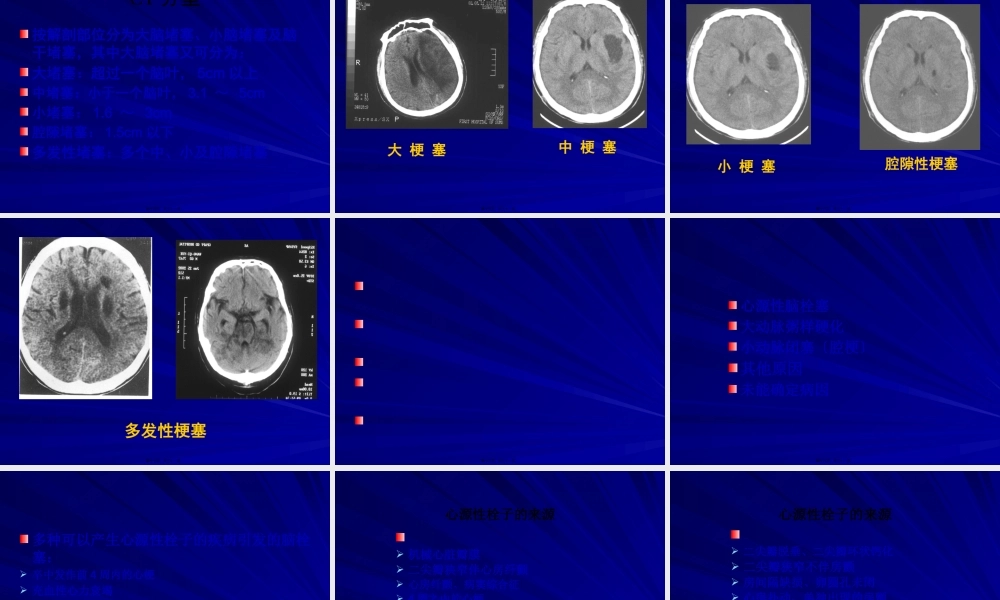

缺血性卒中分型第一页,共三十一页。脑卒中一组疾病共同的临床病理状态多种病因:高血压、动脉硬化、心脏病、糖尿病、动脉炎┄不同发病机制:栓塞、血栓形成、低血压┄众多临床征象组合的综合征:受累血管及堵塞的部位、大小、侧支循环第二页,共三十一页。脑卒中第三页,共三十一页。脑卒中的分型已较多应用的分型社区流调及临床观察:OCSP分型多中心临床药物试验:TOAST、LSR分型〔病因〕临床诊断〔主要病因及机制〕:动脉血栓性、心源性、腔隙性、其他影像学:CT分型第四页,共三十一页。依据临床表现迅速分型,提示受累血管及堵塞灶的大小和部位:完全前循环堵塞〔TACI〕局部前循环堵塞〔PACI〕腔隙性堵塞〔LACI〕后循环堵塞〔POCI〕第五页,共三十一页。TACI第六页,共三十一页。27小时CT48小时CTTACI第七页,共三十一页。PACI-皮层梗塞第八页,共三十一页。PACI-基底节梗塞第九页,共三十一页。LACI-腔隙性梗塞第十页,共三十一页。POCI-小脑和脑桥梗塞第十一页,共三十一页。POCI--中脑堵塞第十二页,共三十一页。POCI-延髓梗塞第十三页,共三十一页。CT分型按解剖部位分为大脑堵塞、小脑堵塞及脑干堵塞,其中大脑堵塞又可分为:大堵塞:超过一个脑叶,5cm以上中堵塞:小于一个脑叶,3.1~5cm小堵塞:1.6~3cm腔隙堵塞:1.5cm以下多发性堵塞:多个中、小及腔隙堵塞第十四页,共三十一页。大梗塞中梗塞第十五页,共三十一页。小梗塞腔隙性梗塞第十六页,共三十一页。多发性梗塞第十七页,共三十一页。第十八页,共三十一页。心源性脑栓塞大动脉粥样硬化小动脉闭塞〔腔梗〕其他原因未能确定病因第十九页,共三十一页。多种可以产生心源性栓子的疾病引发的脑栓塞:卒中发作前4周内的心梗充血性心力衰竭冠状动脉狭窄房颤、房扑、病窦综合征人工心脏瓣膜心室壁运动不能和心室壁运动功能减退心房、心室、主动脉、冠状动脉血栓形成第二十页,共三十一页。心源性栓子的来源机械心脏瓣膜二尖瓣狭窄伴心房纤颤心房纤颤、病窦综合征4周之内的心梗左心房或左心耳、左心室血栓扩张型心肌病左心室区段性运动功能不良左心房粘液瘤感染性心内膜炎第二十一页,共三十一页。心源性栓子的来源二尖瓣脱垂、二尖瓣环状钙化二尖瓣狭窄不伴房颤房间隔缺损、卵圆孔未闭心房扑动、单独出现的房颤生物心脏瓣膜非细菌性血栓性心内膜炎充血性心力衰竭左心室区段性运动功能减退>4周,<6月的心梗第二十二页,共三十一页...